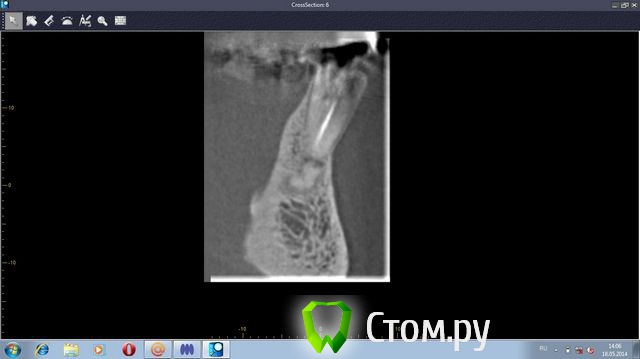

stradalitca Опубликовано 20 мая, 2014 Автор Поделиться Опубликовано 20 мая, 2014 (изменено) Добрый вечер! Я тут ещё глянула как установлен штифт на четвёрке снизу справа. Вот фото в проекциях. Неужели зуб тоже пробит штифтом? или пойдёт ? и я зря переживаю. Изменено 20 мая, 2014 пользователем stradalitca Ссылка на комментарий

Korel Опубликовано 23 мая, 2014 Поделиться Опубликовано 23 мая, 2014 Неужели зуб тоже пробит штифтом? Похоже на то. А Вы не рассматривали для Вашей мамы вариант (на н\чел.) бюгельный протез с замковыми креплениями. 1 Ссылка на комментарий

stradalitca Опубликовано 23 мая, 2014 Автор Поделиться Опубликовано 23 мая, 2014 почитала про мплантанты. Получается, что нам это не особо подходит. Начиная с того, что надо вылечить всю остальную челюсть - то есть убрать очаги воспаления. А воспаление видно невоооружённым глазом. Сегодня у неё стала кровить нижняя четвёрка справа. то ли от полосканий солью, то ли дают знать о себе очередной неудавшийся штифт.А бюгельный протез Вы предлагаете на место моста из 9 коронок и плюс 5,6,7 слева? я правильно поняла? Ссылка на комментарий